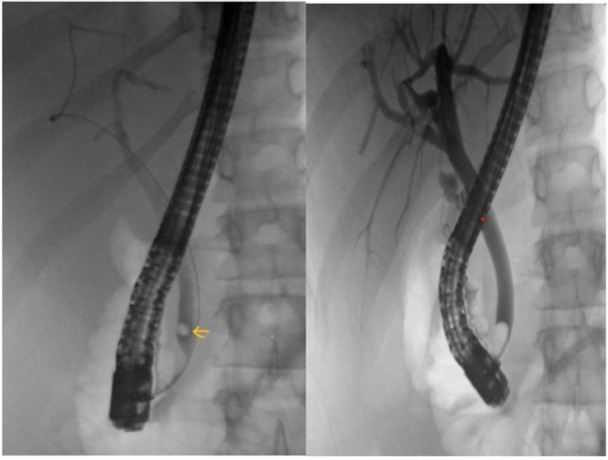

Endoscopic retrograde cholangiopancreatography (ERCP) is a crucial procedure for diagnosing and managing conditions affecting the pancreas and biliary tract. The procedure can be technically challenging and carries risks of complications, with post-ERCP pancreatitis (PEP) being the most common. We report a case of a 16-year-old female who presented with cholelithiasis that progressed to choledocholithiasis which was removed using ERCP. Following this, she developed PEP and subsequently progressed to atypical hemolytic uremic syndrome, a rare complication reported in the pediatric literature.